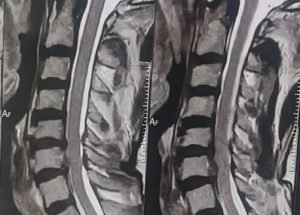

Expert spine services including minimally invasive surgery, pain management, and deformity correction.